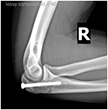

Olecranon Stress Fracture

The patient is an elite baseball pitcher who felt progressive pain in the posterior aspect of his elbow during fall ball. He presented with a stiff shoulder, a diminished arc of motion, and deficiencies in his core musculature. X-rays demonstrated an olecranon stress fracture (far right xray – red arrow). He was shut down from throwing and began to work in physical therapy for his range of motion deficiencies. At two months, the stress fracture showed progression of healing (middle image). By three months, his olecranon stress fracture had healed and he was allowed to begin an interval throwing program (far left xray – red arrow). He returned to pitching at an elite level.